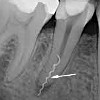

Закрытие перфорации корня зуба

Закрытие перфорации корня зуба. Устранение перфорированного дефекта, при котором корневой канал связывается с тканями пародонта. Перфорация является осложнением эндодонтического лечения, она может привести к развитию пародонтита, разрушению связок и потере зуба. Способ закрытия дефекта зависит от его положения по отношению к корневому каналу (во рту, в средней трети, на вершине). Для герметизации эндодонтической перфорации используются амальгама, стеклоиономерные и композиционные материалы, кальцийсодержащие пасты, триоксидный минеральный заполнитель (ProRuth) ; Манипуляция проводится под контролем стоматологического микроскопа. Целью лечения является создание надежного барьера, предотвращающего распространение инфекции в пробах зубов.